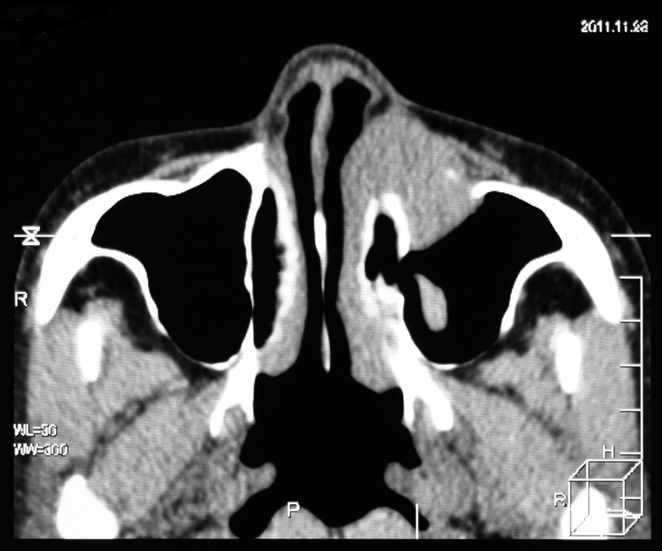

extramedullary plasmacytoma arising in the sinonasal tract

71year old, male

鼻腔内腫瘤生検組織 病理所見